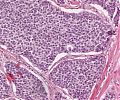

A92 Follikuläres Adenom der Schilddrüse

Randlicher Anteil mit mikrfollikulärem Aufbau (hohe Vergrößerung)

A92 Follikuläres Adenom der Schilddrüse

Randlicher Anteil mit mikrfollikulärem Aufbau (geringe Vergrößerung)

Follikuläres_Adenom1_SD_A92.png

Neoplastische Follikel unterschiedlicher Größe von isomorphen Follikelepithelien mit sog. Resorptionsvakuolen begrenzt

Follikuläres_Adenom_SD_A92.png

Follikulär gebaute Neoplasie mit gemischt mikro und normo-follikulärem Aufbau, umgeben von einer bindegewebigen Pseudokapsel.